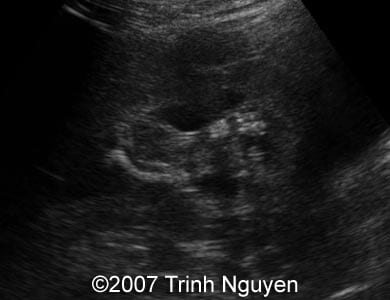

Image 3: The image shows right deformed tibia and partial duplication of the distal part of the right leg.

3

Video 1:  The video shows right deformed tibia and partial duplication of the distal part of the right leg (two feet arise from the common leg).